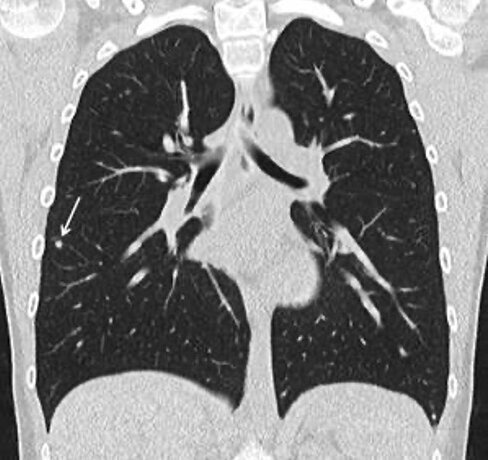

Die grundlegende Voraussetzung für die optimale Darstellung der Herzkranzgefäße mittels CT ist ein moderner Multislice-Scanner.

An der Klinik für Diagnostische und Interventionelle Radiologie am UKS verfügen wir mit dem Siemens FORCE über eine der modernsten Gerätetechniken. Diese ermöglicht sowohl eine extrem schnelle als auch eine besonders strahlungsarme Bildgebung.

Durch die Kombination und gleichzeitige Nutzung von zwei Röntgenröhren in einem Gerät (Dual-Source-Technik) ist es möglich, die Bildaufnahme so weit zu beschleunigen, dass das gesamte Herz mitsamt Herzkranzgefäßen zwischen zwei Herzschlägen aufgenommen wird. Die Schnelligkeit der Aufnahme erlaubt es zudem, auch bei eventuell bestehenden Herzrhythmusstörungen eine hohe Bildqualität zu erzielen.

Die Verwendung empfindlichster Detektoren und modernster Technik sorgt gleichzeitig für eine deutliche Reduktion der Strahlenbelastung. Hierdurch erreichen wir Aufnahmen der Koronararterien mit einer Dosis von unter 1 mSv, was in etwa der Strahlenbelastung einer Mammografie oder von Röntgenaufnahmen des Beckens oder der Lendenwirbelsäule entspricht.